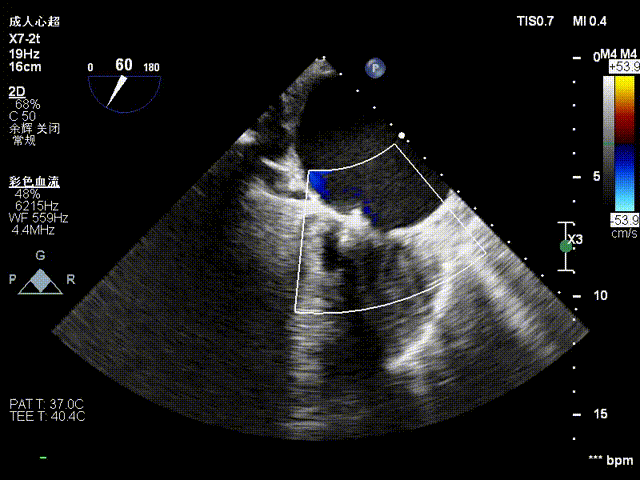

在术者的细致操作下完成瓣叶捕获,再度确认夹合器orientation后操作Gripper down,关闭C6后评估反流量微量即操作解离。影像下显示植入一枚C6可见3区反流明显下降,改善效果明显。

关夹合器

关夹合器评估

夹合器稳定性评估

夹合后反流评估

检查示组织桥明显,夹合器稳定,残余反流明显减少,降低至1+等级,二尖瓣平均跨瓣压差为2mmHg,经团队评估,手术效果达既定预期,各项指标平稳,顺利结束手术。